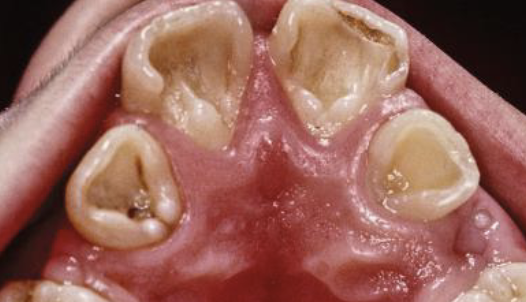

AD, AR, X-linked; both deciduous and permanent dentition are diffusely involved, affects enamel (soft, thin, easily damaged, susceptible to decay), dentin is exposed

amelogenesis imperfecta (AI)

Types of AI

hypoplastic (pitted), hypomaturation/ hypocalcification (snowcapped) AI with taurodontism

Clinical appearance of AI

yellow-brown to white pitted lesions, open bite, loss of contact